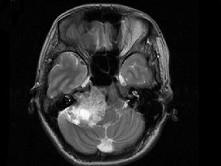

女,45岁,右耳听力下降半年余,CT检查如图,最可能诊断为 ( )

• A.脑膜瘤

• B.继发性胆脂瘤

• C.三叉神经瘤

• D.原发性胆脂瘤

• E.听神经瘤

答案: E